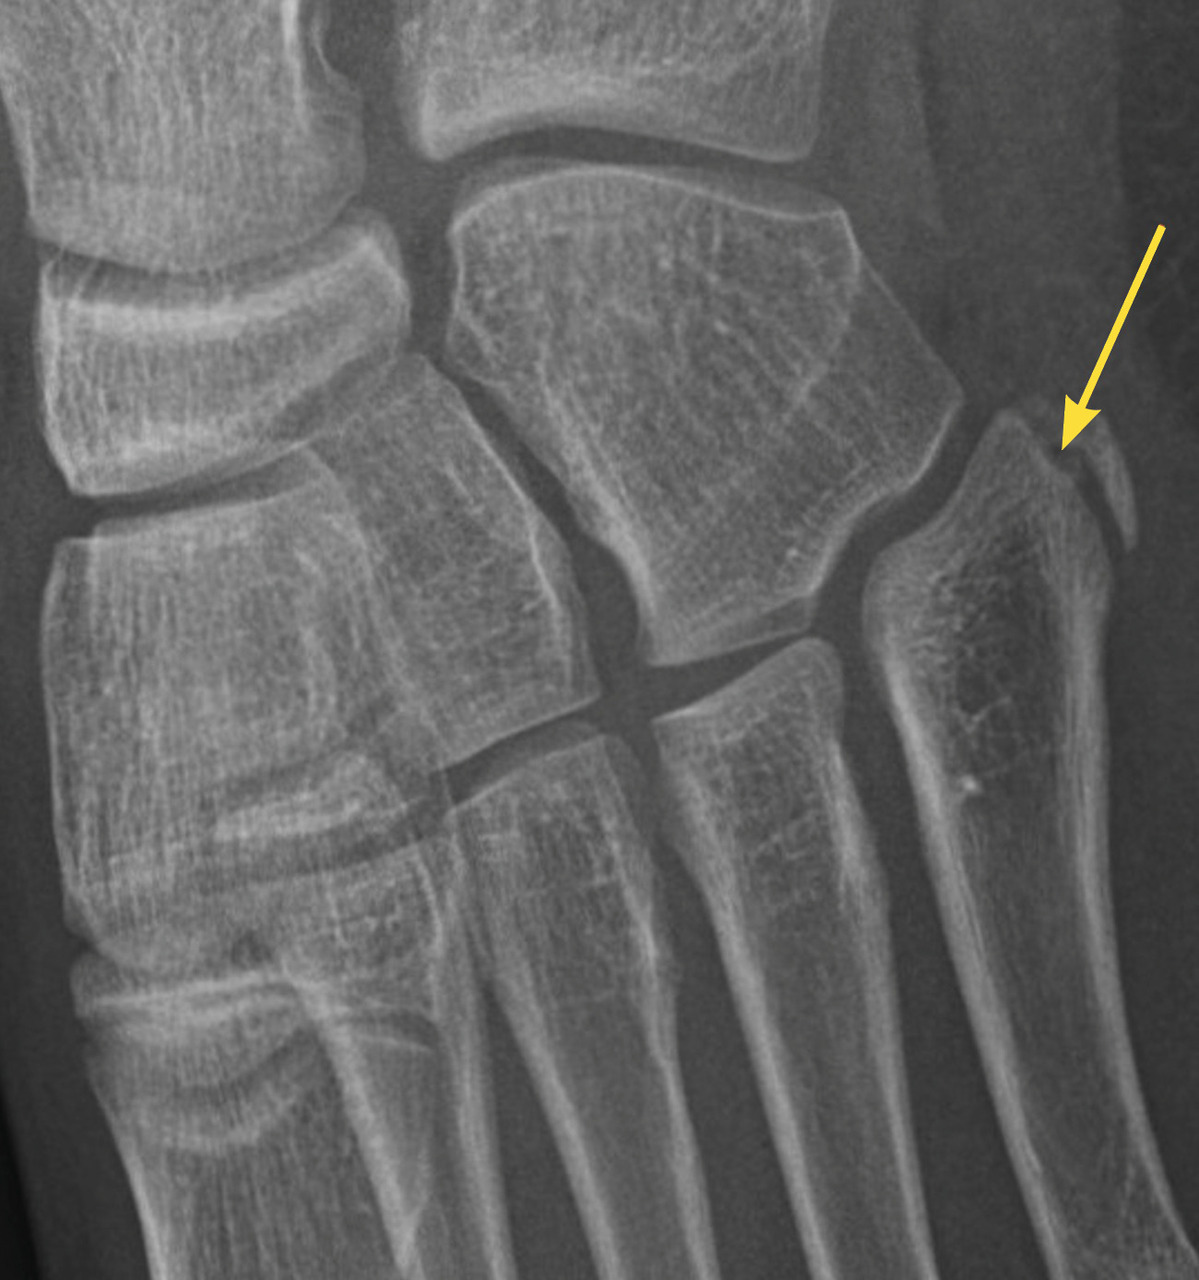

Certaines fractures non ou peu déplacées peuvent être de diagnostic difficile. La fracture de Tillaux touche préférentiellement les adolescentes en fin de croissance, avec une atteinte de l’extrémité distale et latérale de l’épiphyse tibiale. Le tableau clinique mime une entorse de cheville et le trait de fracture n’est pas toujours évident à la radiographie (fig. 3). La fracture étant articulaire, le scanner est souvent nécessaire pour décider d’une ostéosynthèse. Il faut également se méfier des fractures de la base du cinquième méta­tarsien, à ne pas confondre avec le noyau d’ossification secondaire. L’examen clinique permet donc d’orienter le diag­nostic, car la radiographie peut être trompeuse (fig. 4).